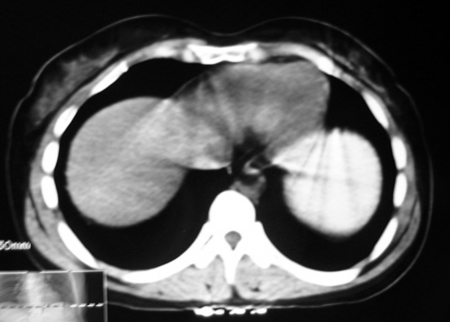

以下是引用bmw011在2009-4-23 13:28:00的发言:[br]考虑右肾包膜下血肿。

以下是引用卜一在2009-4-23 15:43:00的发言:[br]考虑右肾包膜下血肿,不排除占位病变伴出血可能,建议进一步检查。